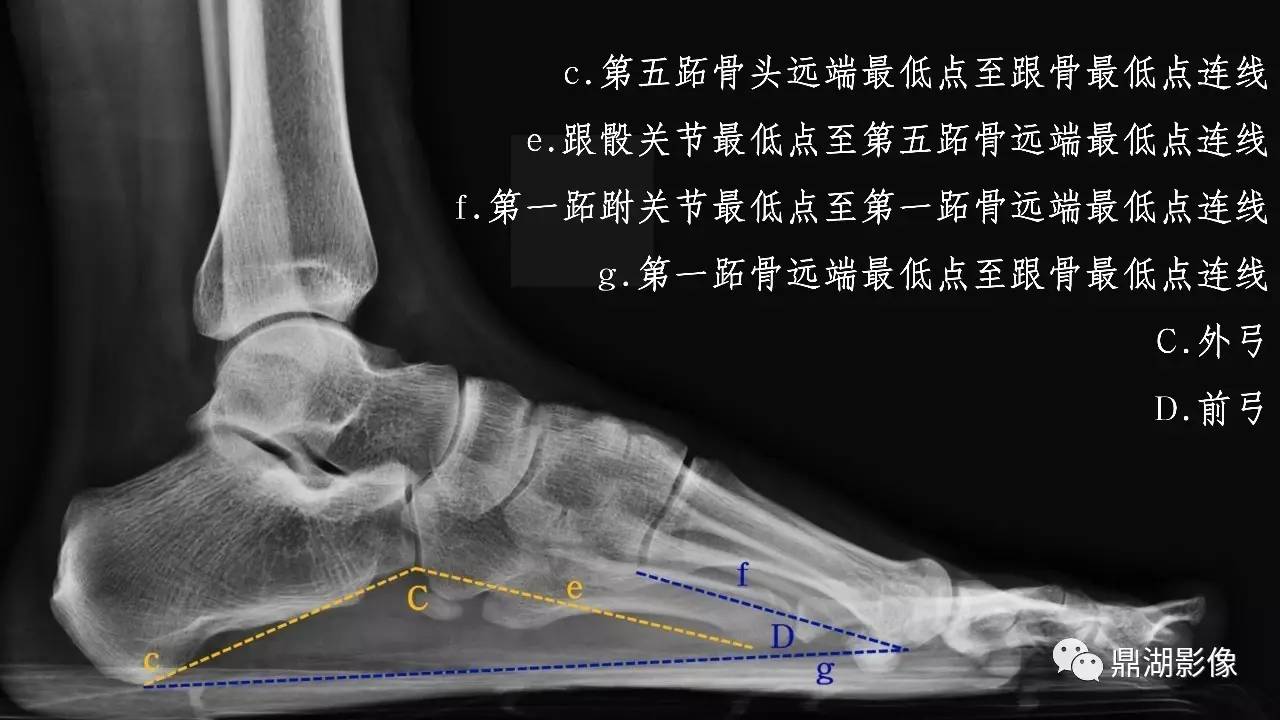

扁平足(平足)指的是正常足弓的缺失,或称为足弓塌陷。值得注意的是,平足不等于平足症,也不是所有的平足都需要治疗。如果平足者合并有疼痛等症状时,就被称为平足症,才可能需要治疗。